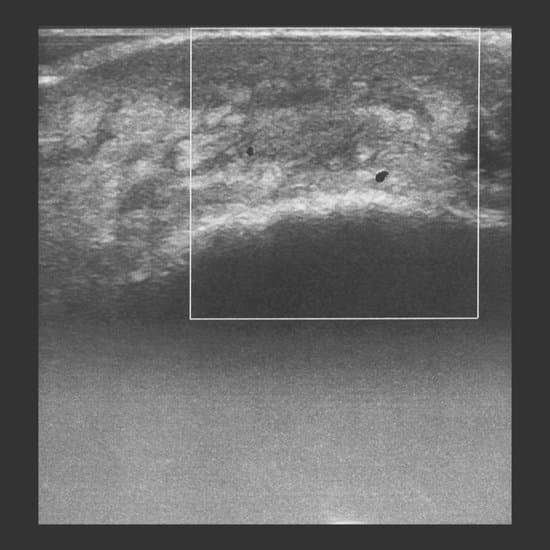

항문 초음파 검사는 항문과 직장 주변 조직을 고주파 음파를 이용해 실시간으로 촬영하는 검사입니다.

방사선 노출이 없고, 간편하게 항문 주변 내부 상태를 파악할 수 있어항문농양, 항문누공, 치열, 치질 같은 질환 진단에 널리 사용됩니다.

3. 내부 조직 스캔

항문관, 직장 부위의 층별 구조를 스캔하여농양, 누공, 괄약근 손상, 염증 유무를 확인합니다.